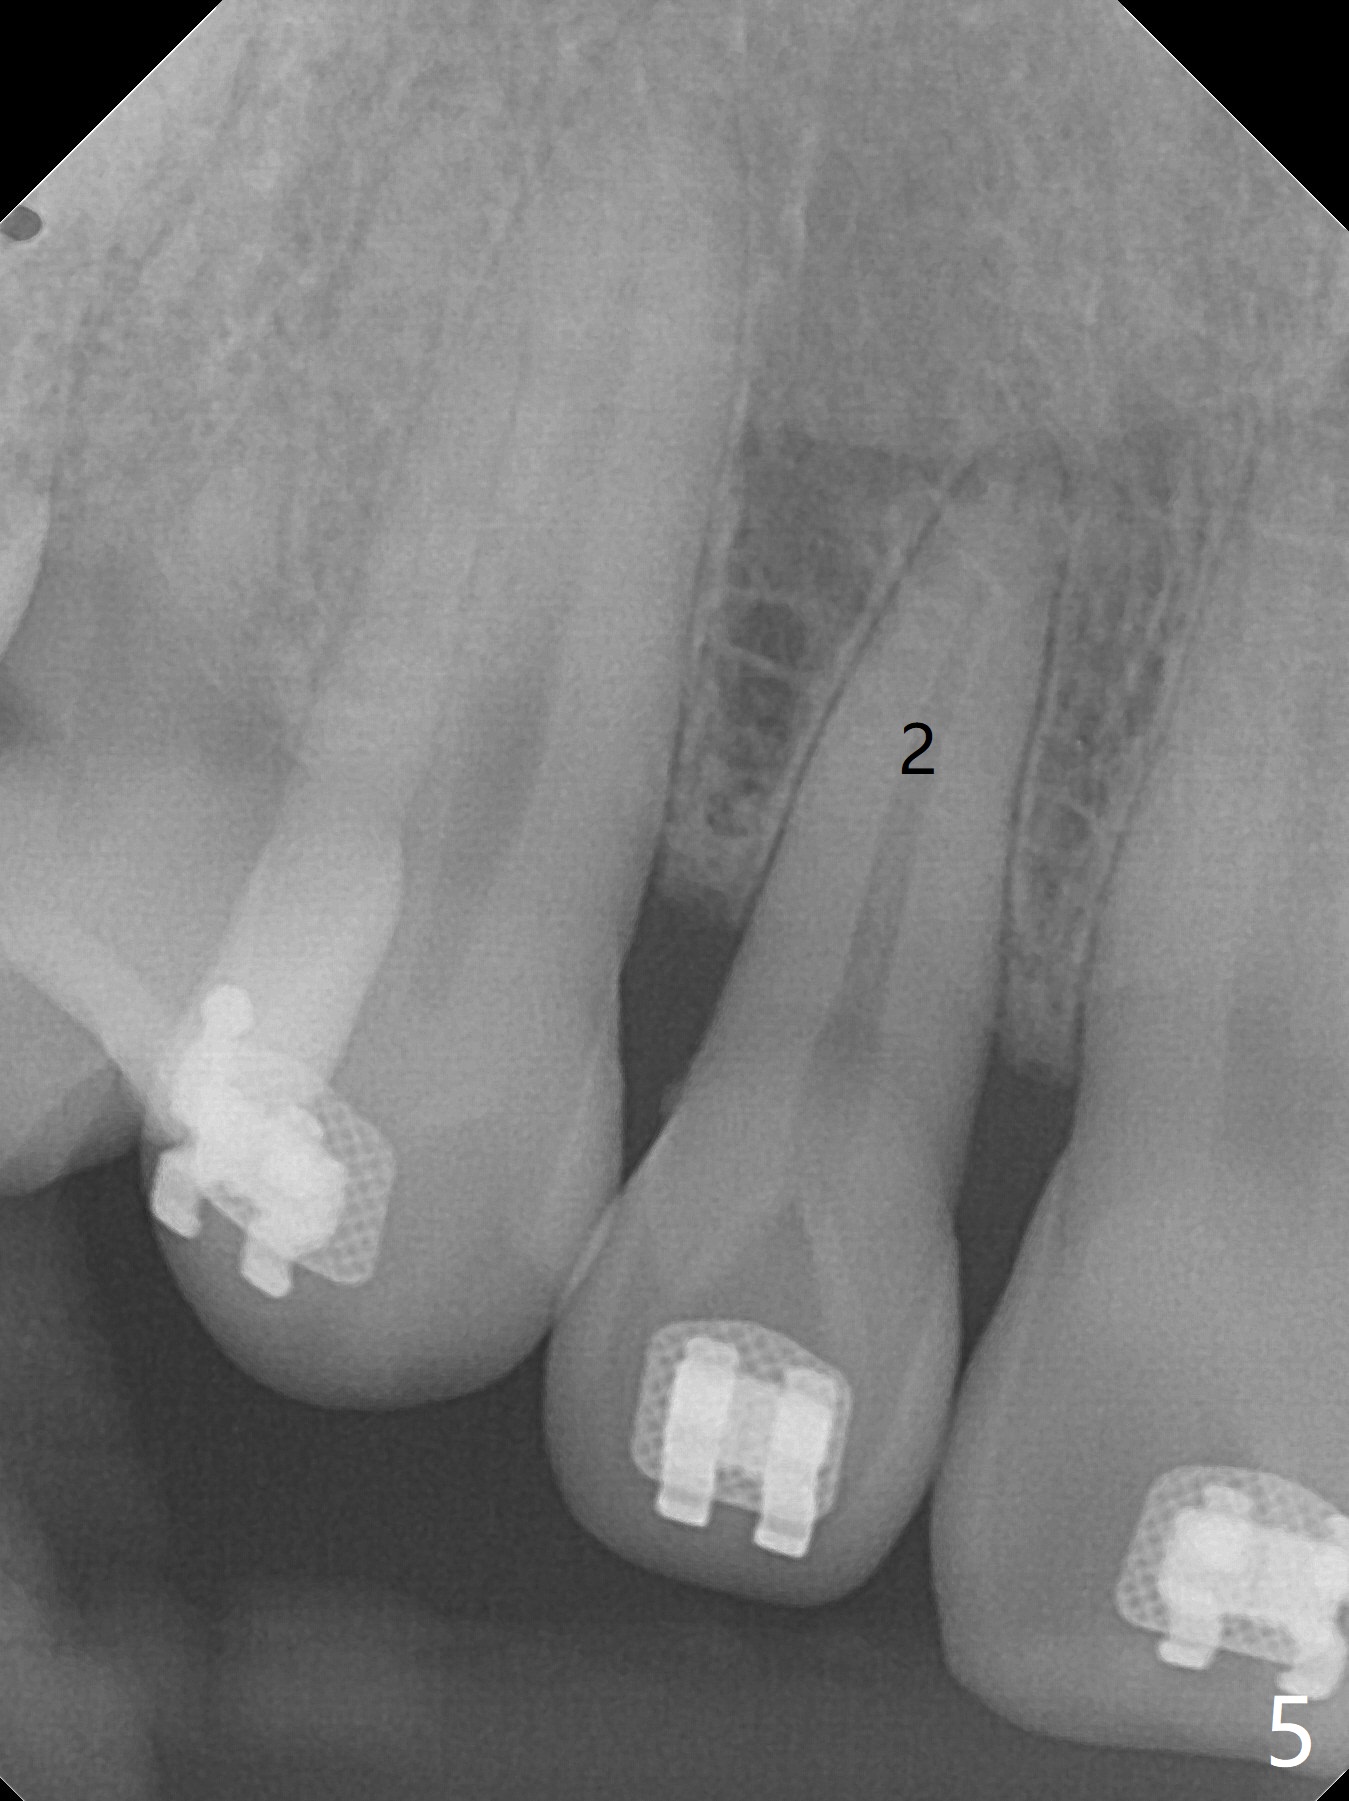

A 40-year-old man requests orthodontics after #17 and 32 extraction. UL5 is missing (Fig.1), while the upper midline deviates to the left (Fig.2 arrow) with crowding between UL2 and 3 (Fig.3). The main goal is to retract UL5 distal and move the upper midline to the right to alleviate UL anterior crowding. Implant will be not needed. To monitor potential root resorption associated with tooth movement, preop PAs are taken (Fig.4-7). The space for an implant at UR5 is narrow. UR4 needs to be distalized using UR7 or a miniimplant distal to UR7 as an anchor (Fig.8). UR4 and 3 will be repositioned to establish Class I occlusion (Fig.9). The space gained by UR4 distalization may be enough to correct the upper midline deviation and UL3 malposition (Fig.10). Brackets will be placed in the lower arch in spite of the normal alignment (Fig.11). UL2 and 3 brackets are unable to be engaged to 14 niti wire (Fig.12). Next visit try to engage UL2 bracket. If not, save the old wire for possible future reuse. Closed spring is placed with 18 ss wire <3 months post banding (coronavirus). Three weeks post closed spring between UR4-7, UR3,4 are being distalized (Fig.13). Distalization of UR4 is not much in 5.5 months (Fig.14,15). It seems necessary to use a miniimplant distal to UR7 as an anchor (Fig.16 white circle), place a long hook mesial to UL4 (more or less root movement instead of tilt) and place the same closed spring between the anchor and hook. In spite of the fact that UR4 seems to have been completely distalized and that UR2 is being distalized 8 months post banding (Fig.18), a 8 mm long mini-implant is placed in the maxillary tuberosity with minimal local anesthetic (Fig.17,19). A longer closed spring (18 mm) is placed between the implant and UR3 hook (Fig.20). Next appointment a lingual button will be placed at UR4 for rotation, while a post hook mesial to UR3 for torque. UR3 distalizes with the help of UR mini-implant, which is unfortunately loose. Next visit place lingual button at UR4 (Fig.21 arrow) to distalize the lingual cusp. Crimpable power hook is placed mesial to UR2 for distalization (for root torque, Fig.22). If it works, remove the wire and reposition the hook for UR1 next visit. UR2 is distalized in one appointment (~ 1 month, Fig.23, as compared to Fig.22). With lingual button at UR4, rotation seems to have been corrected shortly (Fig.24 arrow).